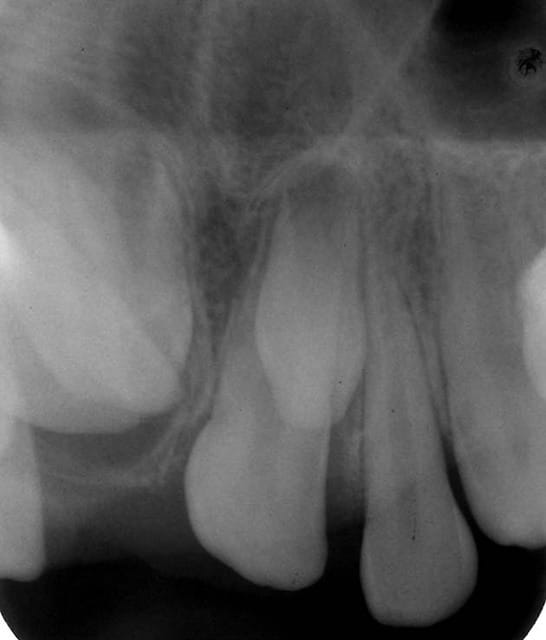

Premier cas , radiographies 11a et 21a ,

chez un garçon de 12 ans .

La 11 est retenue en rotation avec une mésiodens en position palatine .

La 21 est en normoposition avec également une mésiodens en position palatine .

TRT : exerèse des deux dents surnuméraires puis repositionnement orthodontique de 11 .